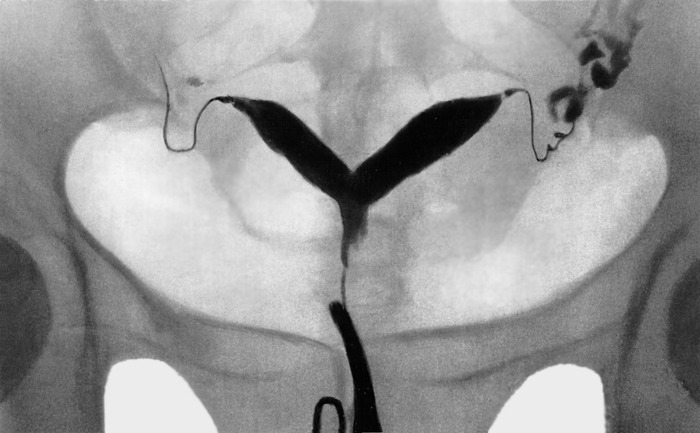

Метросальпингографические данные при двурогой матке

Наиболее достоверно характерные признаки седловидной матки обнаруживаются при проведении гистеросальпингографии: на рентгенограммах определяются 2 устья фаллопиевых труб, в области дна отчетливо читается небольшое углубление в виде седла, вдающееся в полость матки. Аналогичные признаки выявляются при проведении ЯМРТ. Гистероскопия используется для непосредственного визуального обследования полости матки. В процессе ведения беременности у пациенток с седловидной маткой осуществляется мониторинг допплерографии маточно-плацентарного кровотока, проводится кардиотокография, фонокардиография плода.